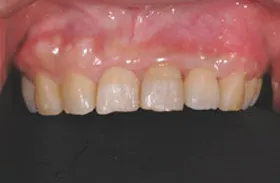

むし歯による前歯欠損の為来院されたケース

治療のポイント

歯の根の位置を引き上げ、抜歯。その日にインプラント治療へ。

自然の歯と変わらない審美性を取り戻し、非常に満足されています。

| 主訴 | 上顎の真ん中の歯が折れた |

| 治療方法 | 歯の根を引き上げることにより、増骨するので、その後1本のインプラントを埋入し治療した |

| 治療期間 | 約1年 |

| 通院回数等 | 10回 |

| 費用 | 550,000円(税込) |

| リスク・副作用 | 外科治療なしで増骨させた為、治療期間が長くなった |